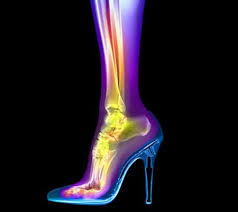

High Heels are Worse than We Thought !

As podiatrist we see the changes that happen to women’s feet from long term wearing of high heel including worsening bunion, hammertoes, metatarsalgia, ankle equinus, and Achilles tendinitis pathology.  In this research it was demonstrated that when women that rarely wore heels walked, their tendons (for example the Achilles tendon) elongated and stretched as expected, whereas in the group of women that regularly wore heels, their tendons were not as engaged but rather the muscle belly attached to the same tendon. This leads to more rigid function which can progress to tendinitis and potential abnormal pull.  Previous research has shown the greatest strength and efficiency of the muscle/tendon unit occurs when the muscle stays relatively the same length and the tendon lengthens.  This also happened when the heel wearing women walked barefoot.  The alteration of the muscle function puts these women at higher risk for tendinitis, especially when wearing tennis shoes and flats when more stretch is required by the tendon to place the heel on the ground.

The recommendation was not to stop wearing heels, but rather to slowly lower the heel height worn and to reserve the extra high heels for 1-2 times a week.